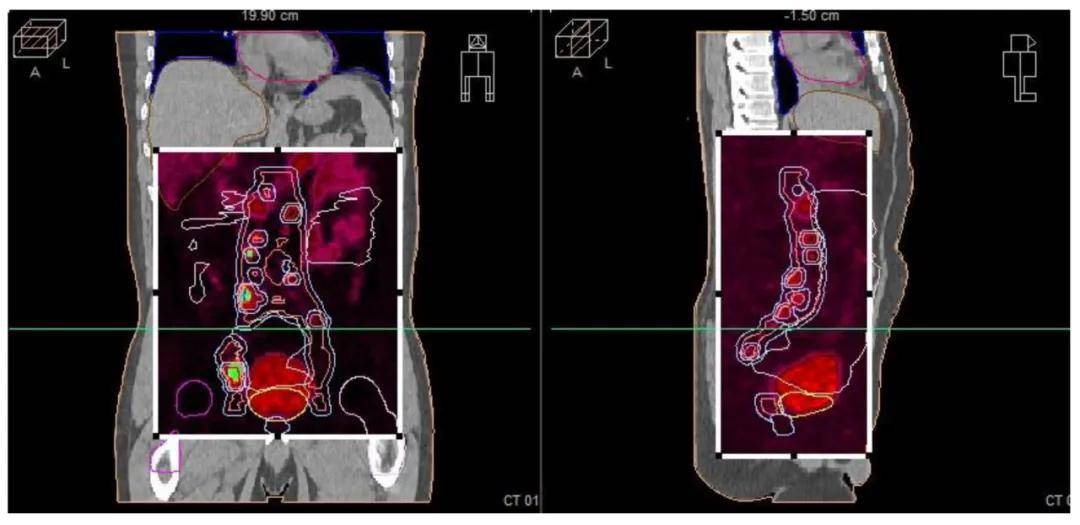

本研究提出一种针对广泛转移性前列腺癌的综合治疗方案。一名57岁男性患者因PSA水平升高入院 (图1),经全面评估后,先接受比卡鲁胺治疗,并通过PET/PSMA等影像学检查明确癌症分布。随后,患者接受雄激素剥夺疗法及多西他赛化疗。因疾病仍有活动迹象,故采用放疗巩固,包括针对前列腺和转移淋巴结的远程放疗 (图2) 及前列腺的高剂量率近距离放疗 (图3)。

患者初始PSA高达280 ng/mL,前列腺活检确诊为腺癌,Gleason评分7,WHO分级3。CT显示广泛盆腔淋巴结转移,PET/PSMA影像 (图4) 揭示前列腺及淋巴结高代谢活性。患者被诊断为cT2N1M1a期前列腺癌。经多西他赛化疗,PSA水平有所下降,但CT仍示广泛转移。随后进行放疗,PET-CT (图5) 显示前列腺及淋巴结仍具活性。放疗后,患者PSA降至检测限下,实现完全生化缓解,此疗效经随访影像及临床评估确认。

本病例报告了一例广泛转移性前列腺癌患者,通过多模式治疗实现显著临床反应的过程。患者初诊时PSA水平高,Gleason评分7,提示肿瘤分级高且转移负荷大。经CT、骨显像和PET/PSMA影像诊断,确认存在广泛淋巴结转移,但无骨转移。尽管患者先后接受比卡鲁胺、亮丙瑞林及多西他赛化疗,疾病仍表现出活性。因此,采用转移导向放疗 (MDRT) 作为巩固治疗,包括外照射放疗和高剂量率近距离放疗,针对原发肿瘤和转移淋巴结,实现最大局部控制。放疗后,患者PSA水平降至检测限以下,表明完全生化缓解,挑战了传统寡转移疾病的界限。此外,病例强调了生物标志物如IL-1在优化放疗效果中的重要性,以及多模式治疗的价值。未来研究需进一步验证这些发现,并探索更广泛人群的适用性。